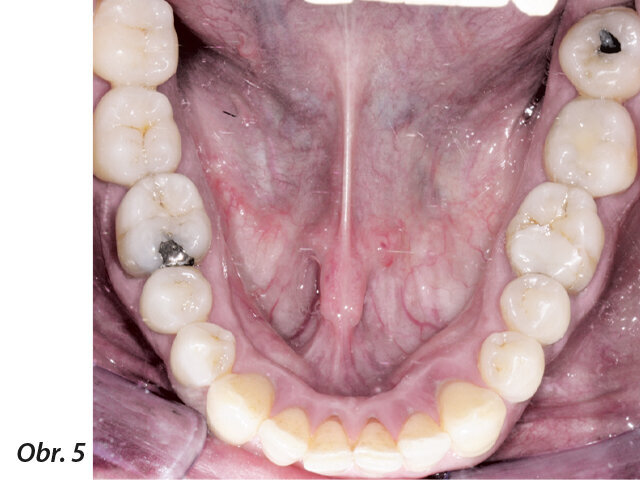

Obr. 1–5: Fotografi cká dokumentace počátečního stavu před parodontologickým ošetřením

49letý pacient přišel na naše oddělení se stížností na krvácení dásní a rozestupování frontálních zubů (obr. 1–5).